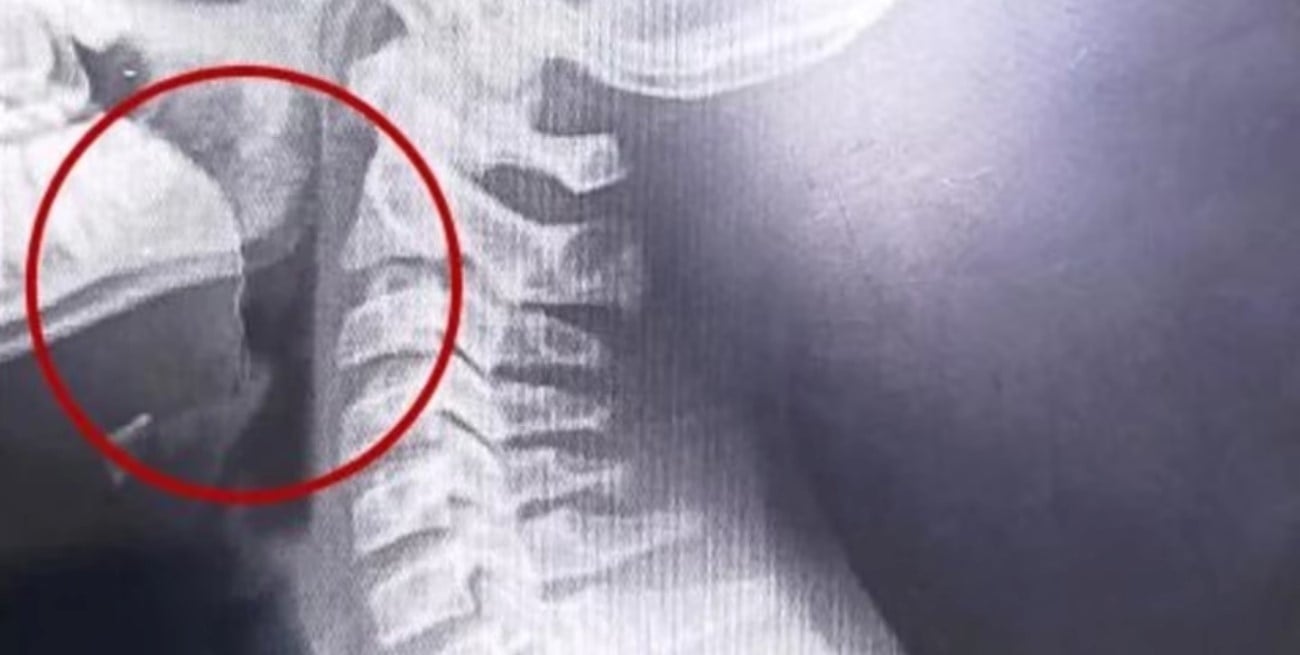

Las placas revelaron la presencia de un objeto extraño en la vía aérea superior. A partir de ese hallazgo, el equipo médico decidió avanzar con una laringoscopía, un procedimiento que permitió observar directamente la zona afectada.

Durante la intervención, los especialistas detectaron un elemento inusual: un alambre fino que se encontraba incrustado en la garganta del adolescente. Este objeto habría sido ingerido accidentalmente junto con la galletita, provocando las lesiones internas, el sangrado y la dificultad respiratoria.